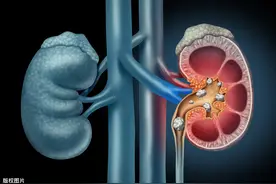

说到憋尿这事儿相信大家都经历过很多人都觉得憋尿顶多就是难受一会儿其实,它对身体的危害远超你的想象近日,河北省胸科医院泌尿外科就接诊了一位因为憋尿导致膀胱破裂的患者男子喝啤酒后去打篮球憋尿致膀胱破裂近日,王先生(化名)因肚子疼前去河北省胸科医院就诊。